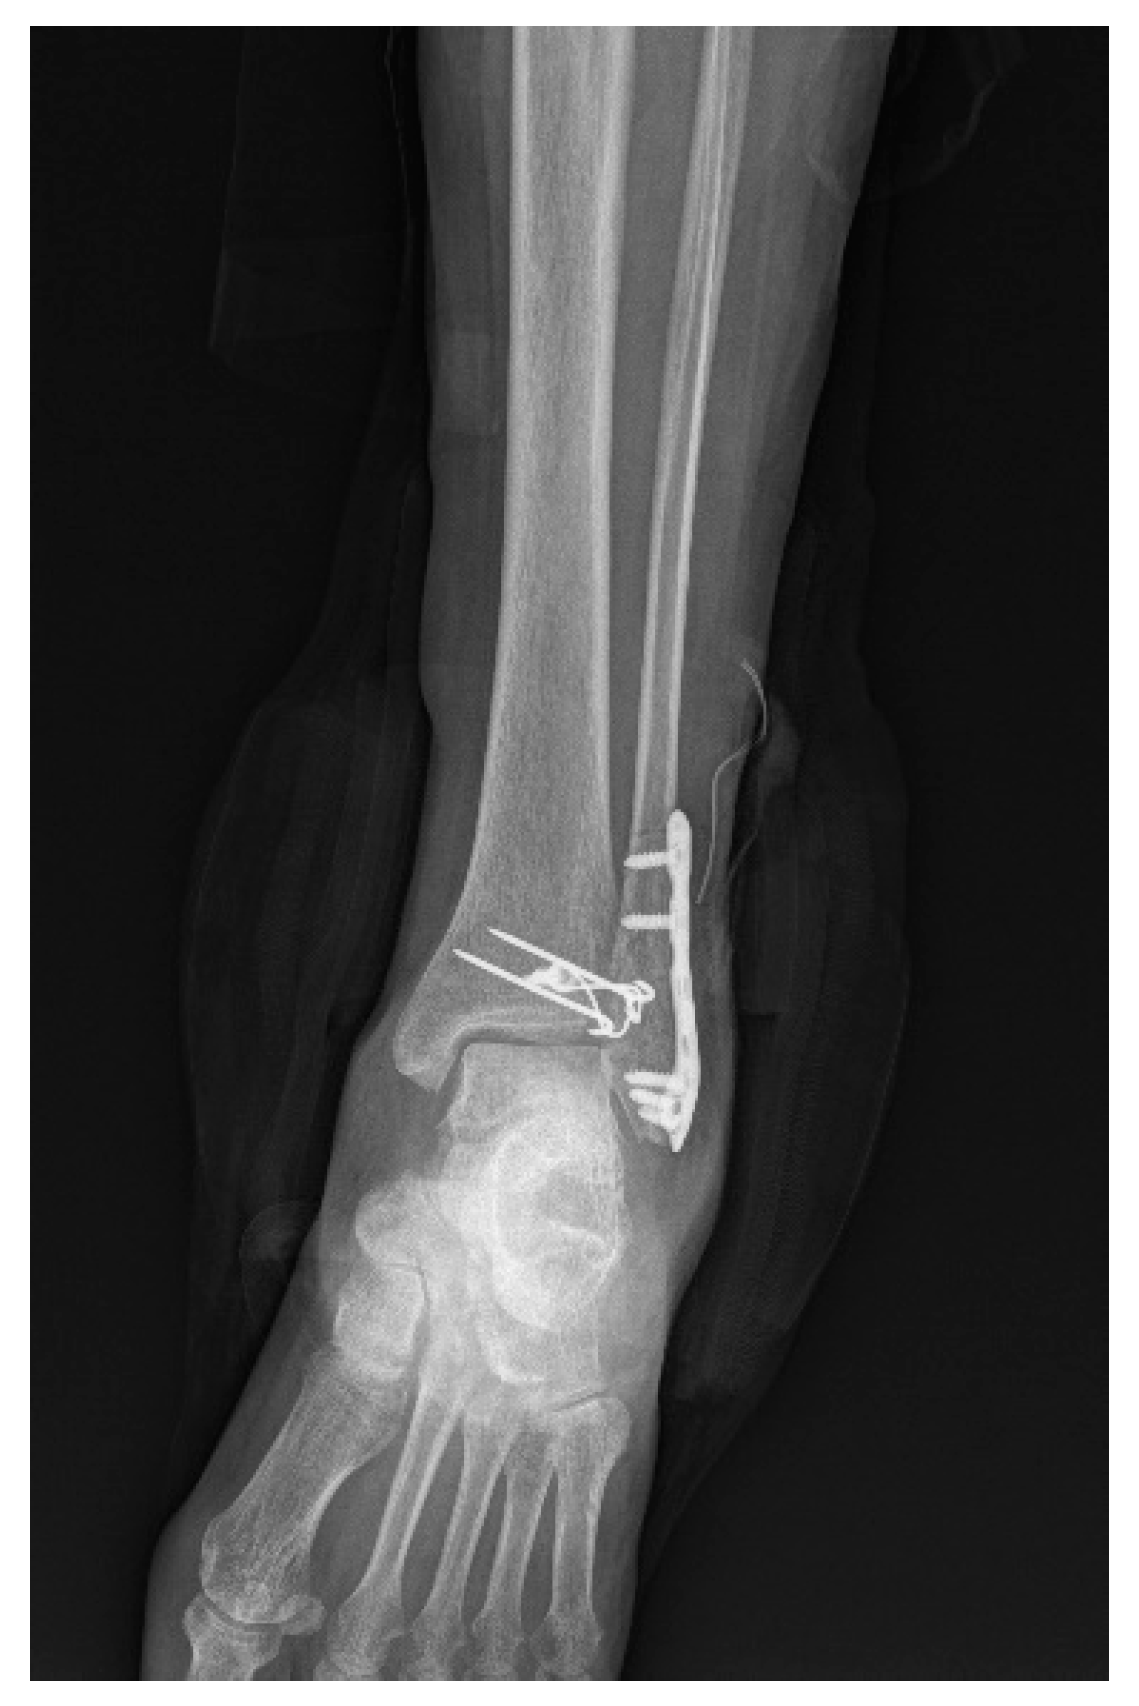

2.4. Surgery

- Yeo, E.D.; Jung, K.J.; Hong, Y.C.; Hong, C.H.; Lee, H.S.; Won, S.H.; Yoon, S.J.; Kim, S.H.; Ji, J.Y.; Lee, D.W.; et al. A Tension-Band Wiring Technique for Direct Fixation of a Chaput Tubercle Fracture: Technical Note. Medicina 2022, 58, 1005. [Google Scholar] [CrossRef] [PubMed]